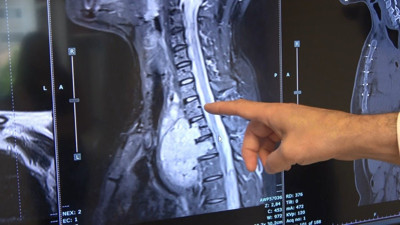

Rektör hastayla sohbet etti. Cerrahlar tümörü çıkardı Ege Üniversitesi Tıp Fakültesi Hastanesinde gerçekleşen beyin ameliyatında Rektör Prof. Dr. Necdet Budak, 63 yaşındaki Mehmet Hürriyet Karcı ile ameliyat sırasında sohbet etti, cerrahlarda büyük bir titizlikle tümörü çıkardı.

Bilinci açık 7 saatlik beyin ameliyatı oldu 24 yaşındaki İskoç Brooke MacFadyen, yaz boyunca geçirdiği nöbet sonrası teşhis konulan beyin tümörünü almak için 7 saat süren zorlu bir ameliyat geçirdi. Bilinci açık şekilde yapılan bu hassas operasyon sırasında, yeni bir dijital izleme sistemi sayesinde doktorlar hastanın tepkilerini anlık izleyerek süreci güvenli hale getirdi.